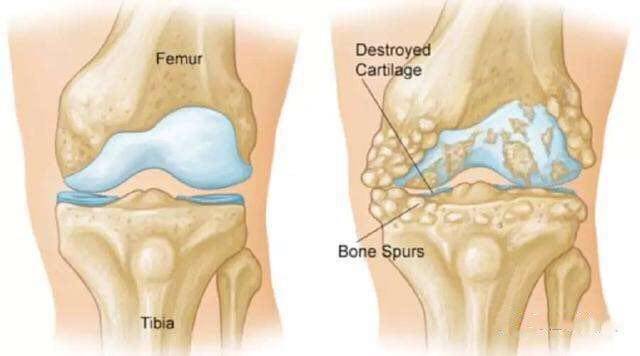

当膝关节骨关节炎遇上间充质干细胞

8月14日发表在PNAS上的一项研究,来自哈佛大学的古人类学家IanWallace和DanielLieberman及其同事研究了近2600具保存在研究或教学中的骨骼,自1940年以来,膝盖骨关节炎的发病率已经增加了一倍多,从6%上升到16%。膝...